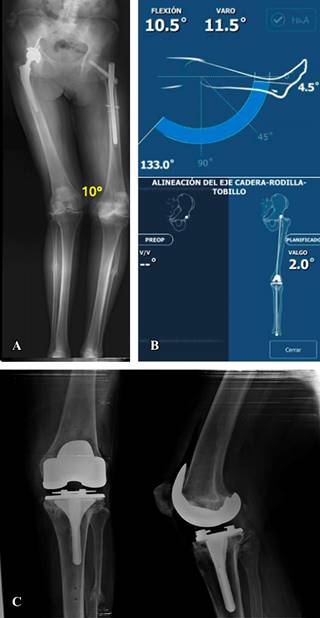

Nueve casos presentaron deformidad en varo (Figura 1) con un promedio de 8.89o. La alineación final resultante en cinco casos fue de 2.3o de varo en promedio, dos casos finalizaron con alineación neutra y dos con valgo de 1o.

Figura 1: A) Eje mecánico de los miembros inferiores de un caso con un clavo centromedular de cadera izquierda y deformidad angular de rodilla en varo de 10o en la rodilla ipsilateral. B) Análisis de movilidad y alineación postoperatoria con cirugía robótica (rango de movilidad de 4.5 a 133o) y alineación final en valgo de 2o. C) Radiografía postoperatoria con prótesis de rodilla estabilizada posterior y vástago tibial de 80 mm.